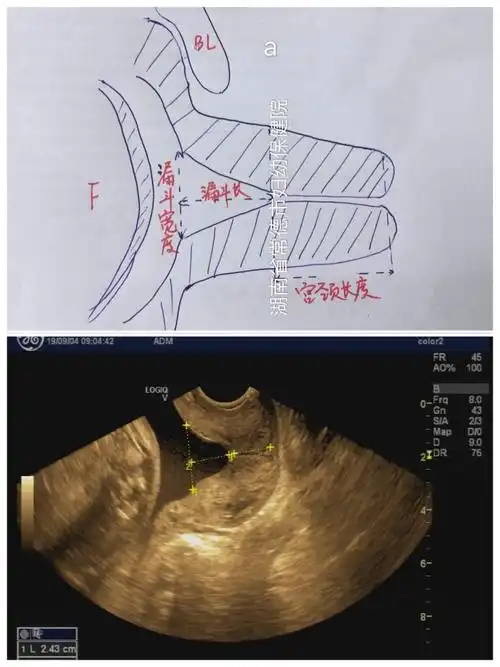

如何测量宫颈漏斗宫颈长度?

0cm 前后径:3.0~4.0cm 横径:4.0~5.0cm 宫颈长度:2.5~3.